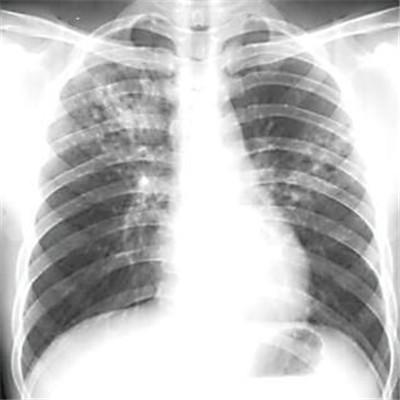

肺结核晚期症状 肺结核晚期症状及表现

肺结核晚期症状时什么?其实这个话题是我最不喜欢提起的,因为在中国现在的肺结核患者真是太多了,在云南等地都有肺结核村,而且我的一个姨夫就是得了肺结核最后不治而亡的,那么肺结核晚期症状是怎样的?